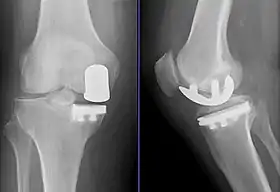

![]() Radiographs of a knee arthroplasty of the medial compartment | |